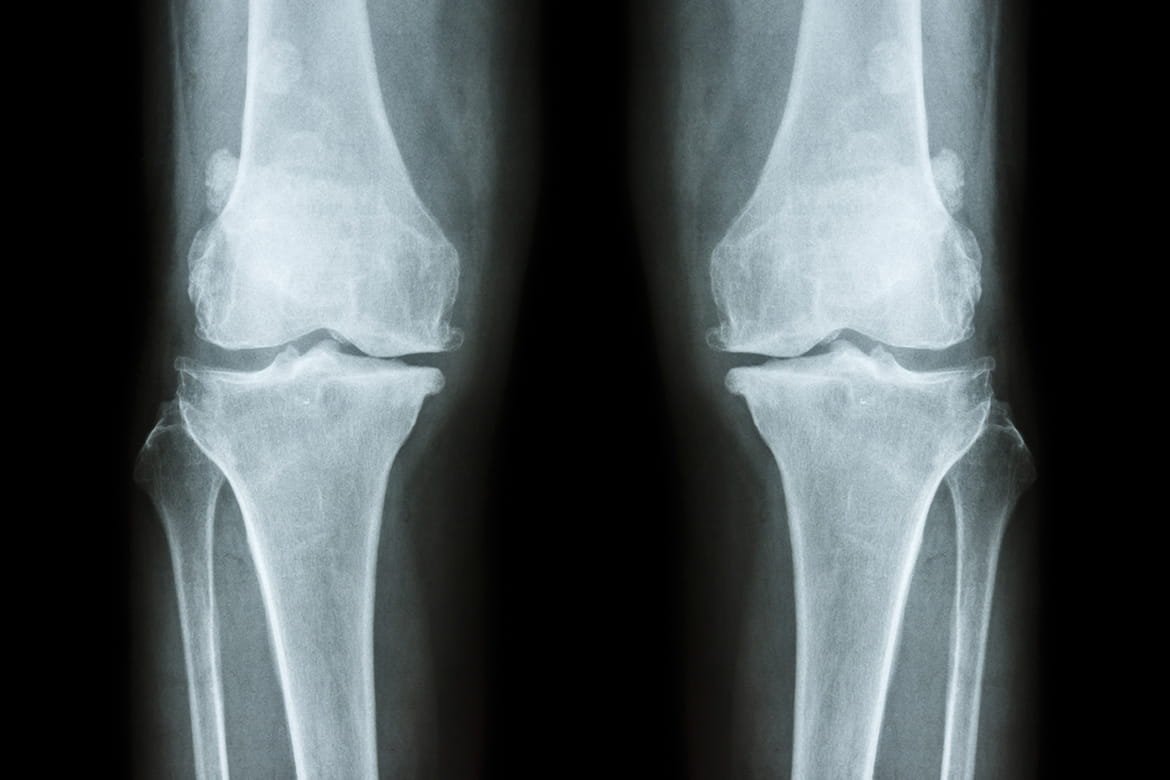

| Osteophytes | New bone formation at the margin of a joint due to degenerative condition of the articular surface. | ![]() |